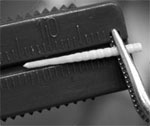

Dacă este necesar, pentru a asigura o imersiune mai completă a pinului în canal, corectați partea apicală a știftului cu burr de diamant. Pentru a controla cu exactitate adâncimea de imersiune, ar trebui să se utilizeze o riglă endodontică.

La exercițiile rădăcină care alcătuiesc setul de Crown post (PD, Elveția) sunt din metal special pentru restrânsă, care permit să înregistreze cu exactitate adâncimea de scufundare a burghiului și verificați adâncimea de scufundare introdus în canalul din fibra de sticla pin.